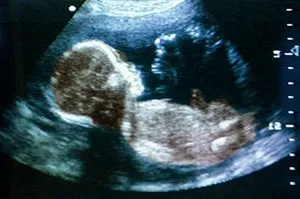

თუ ეწვობთ, რომ ნაყოფის მენჯით წინამდებარეობას აქვს ადგილი, იცოდეთ, რომ საბოლოო დიაგნოზი ისმება ულტრაბგერითი გამოკვლევის საფუძველზე.

ფეხმძიმობის 38-ე კვირაზე ნაყოფის ზომა 48-50 სმ-ია, ხოლო წონა 3000-3100 გრამს აღწევს. ამ პერიოდში ბავშვი უკვე ემზადება ახალ სამყაროსთან შესახვედრად.